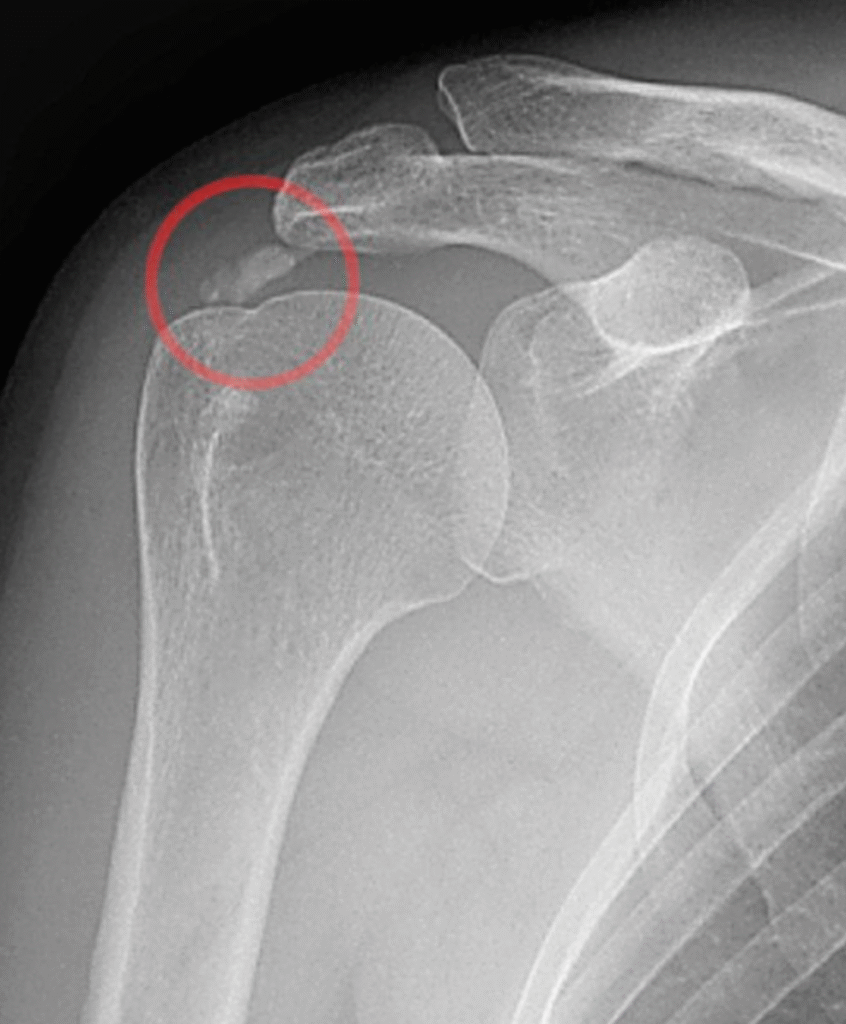

Radiografias: indicadas para investigar calcificações e artrose

4. Tendinite calcária

A tendinite calcária ocorre quando há depósito de cristais de cálcio dentro dos tendões do ombro, principalmente no supraespinal, que faz parte do manguito rotador.

Punção guiada por ultrassom, para remoção dos depósitos de cálcio em casos persistentes